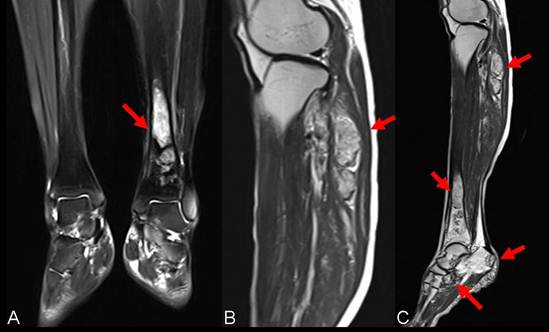

Figure 2

Presurgical MRI examinations. A: MRI showed intramedullary solid lesion covering the distal tibia bone without breaking articular surfaces. T2 weighted image showed the lesion as a high signal (arrow). B: MRI manifested multiple independent solid lesions in the gastrocnemius muscle at the level of the head of the fibula and multifocal lesion with irregular borders at the upper fibula (arrow). C:MRI examination of left lower leg revealed the occult lesions of calcaneus close to the calcaneal tubercle (arrow).

A 59-year-old female patient visited our orthopaedics clinic with complaints of increasing swelling, pain, anesthesia of the left lateral lower leg and extension loss of the left great toe of six months duration. On physical examination a 2.0 cm mass showing tender and palpable was located on the posterolateral aspect of the proximal lower leg, appearing to arise from the left fibular head. A positive Tinel sign at the proximal fibula led us to suspect compressive neuropathy of the peroneal nerve. Radiographs showed a lytic lesion causing irregular cortical bone thinning in the body of the upper fibula with a surrounding slight soft tissue swelling (Figure 1 A). Then we made further both lower extremities X-ray examination, found the similar osteolytic lesion in the distal tibia and cuboid bone (Figure 1 B,C). Routine blood laboratory data were within normal limits at the time and the patient had no previous history of tumor and family history of tumor. However, magnetic resonance image (MRI) for left lower extremity manifested multiple solid lesions in the gastrocnemius muscle at the level of the head of the fibula and multifocal lesion with irregular borders at the upper fibula, distal tibia, cuboid bone and calcaneus (Figure 2). Right lower extremity and other parts of the left lower extremity were apparently normal. The chest radiograph was normal. Histopathological examination of the needle aspiration biopsies from cuboid bone and tibia showed a neoplastic infiltration composed of vascular structures of different caliber lined with mild atypical endothelial cells in a myxoid stroma. The epithelioid cytomorphology were polygonal or spindle shaped, which had vesicular nuclei, unapparent nucleoli and eosinophilic cytoplasm with intractyloplasmic vacuoles and were easily identified (Figure 3). Immunohistochemical study showed immunoreactivity for SMA, CD31, CD34, CD68 and vimentin. No immunoreaction was observed for epithelial membrane antigen (EMA). Owing to these findings; there was not much doubt that the patient was diagnosed as multifocal epithelioid hemangioendothelioma.